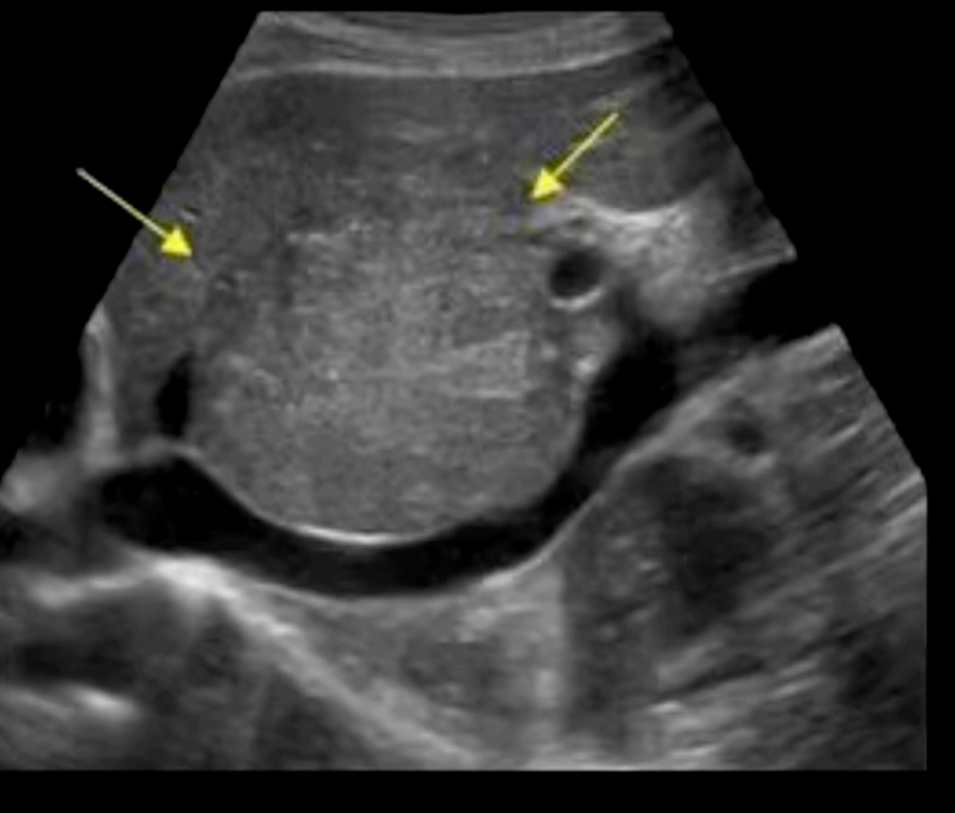

Which of these liver masses/nodules is a malignant tumor.

B-mode ultrasonography is highly sensitive for detecting focal liver lesions but is poorly specific for lesion type. Hepatic masses may appear:

• Hypoechoic, hyperechoic, or mixed echogenicity

• Well-marginated or irregular

• Solitary or multifocal

Importantly, echogenicity does not correlate reliably with malignancy. Multiple studies have demonstrated substantial overlap in the sonographic appearance of benign nodules, primary hepatic tumors, and metastatic lesions (Nyland et al., 2002; O’Brien et al., 2004)

In a large retrospective study of canine liver tumors, no consistent B-mode ultrasonographic features reliably differentiated hepatocellular carcinoma, cholangiocarcinoma, sarcoma, or metastatic lesions, aside from lesion distribution (O’Brien et al., 2004). Hepatocellular carcinomas were more likely to be solitary, whereas sarcomas and metastases were more often multifocal, but significant overlap existed.

Correct answer